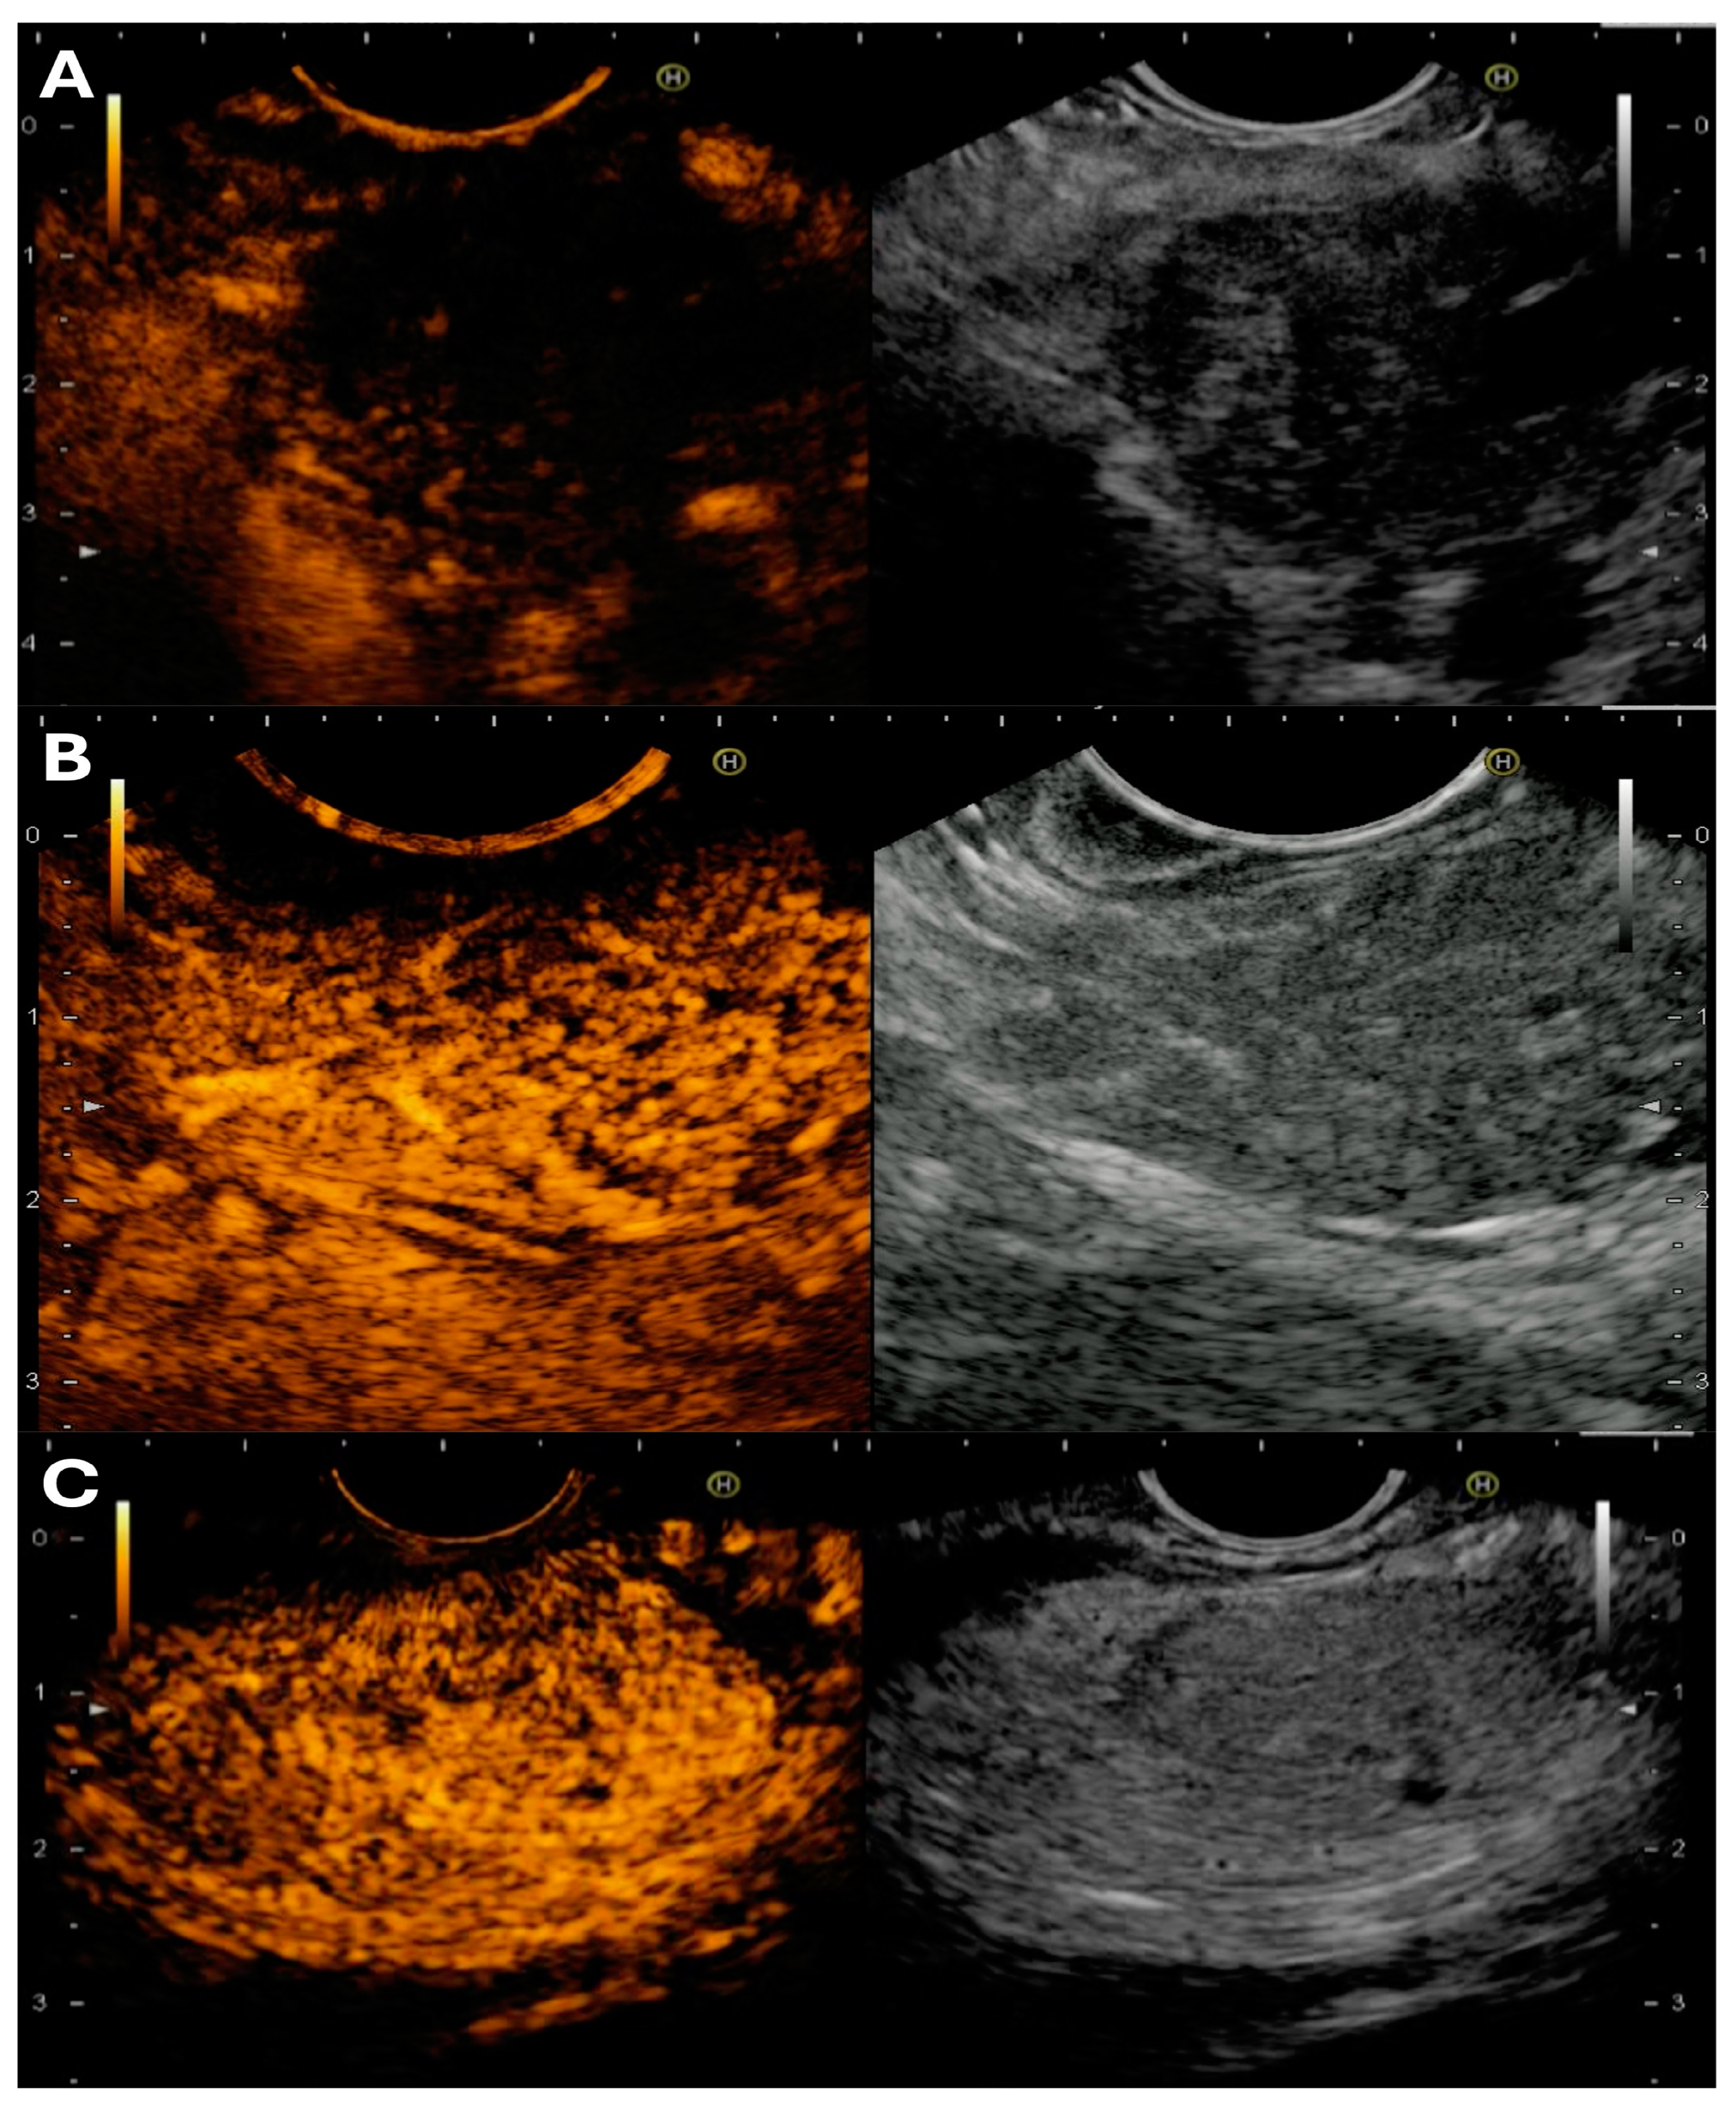

3.4.1. Technique of Performing Advanced EUS Imaging

3.4.2. Basic Interpretation of Findings on CH-EUS and EUS-E